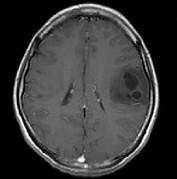

问题 女,33岁,三个月前有右上肢及右颜面部麻木,伴耳鸣及头昏,请根据所提供图像,选择最可能的诊断()

选项 A.脑脓肿 B.星形细胞瘤 C.脑结核 D.脑转移瘤 E.脑血吸虫病

答案 B